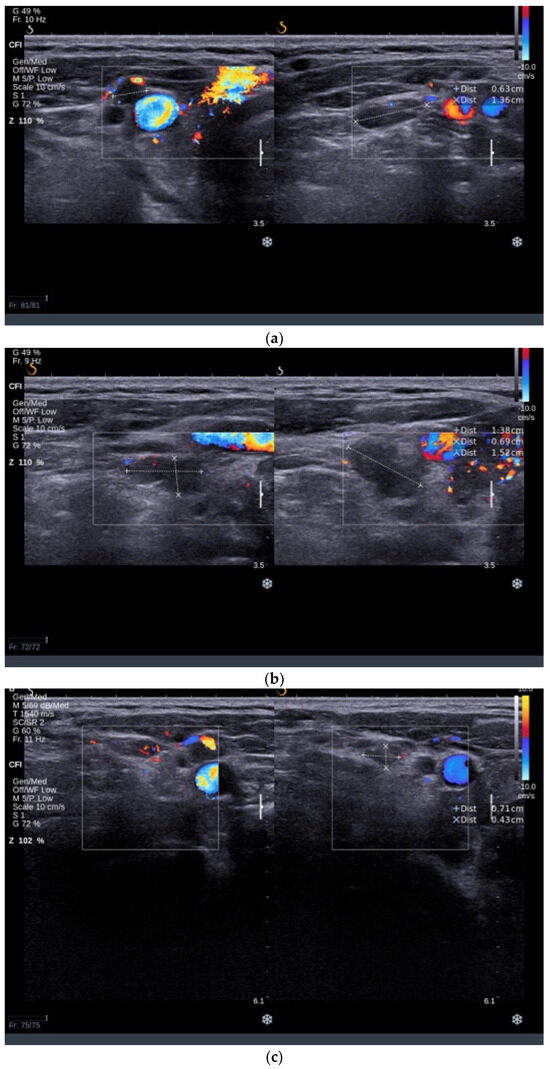

3.3.2. Thyroid Ultrasound

An ultrasound examination revealed an increased thyroid volume of 38 mL with hypoechoic and inhomogeneous parenchyma with increased vascularity. A solid hypoechoic nodule with a diameter of 10/13/15 mm was found in the RTL with ill-defined margins and no vascularity, ACR-TIRADS 5 (Figure 4a). Multiple small solid nodular lesions with similar features were found in the LTL (Figure 4b). Bilateral latero-cervical lymph nodes were enlarged with a round shape, absent central hilum, and subcapsular vascularity (Figure 5a–d), raising concerns about the nature of the nodular lesions present in the thyroid.

Figure 5.

Parts (a–d) showing multiple enlarged lymph nodes with round shape and absent central hilar vascularity.